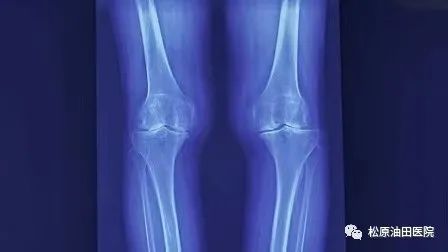

据了解,膝关节骨性关节炎是一种严重影响患者生活质量的关节退行性疾病,其发生率逐年增加,随着我国老龄化的到来,该病已成为第四大致残性疾病,中老年人群多发,且多为女性患者。影像学上表现关节间隙狭窄,关节边缘形成骨赘,其临床表现主要为过度劳累及长期行走时膝关节内测疼痛,休息后疼痛症状缓解,部分患者膝关节肿胀积液,累计内侧间室逐渐发展成为膝关节内翻畸形,常常导致严重疼痛及功能障碍,严重影响患者的生活质量,给患者、家庭和社会造成了沉重的负担。

据悉,今年松原吉林油田医院放射线科引进开展负重位下肢全长的影像系统检查项目,它可以全面观察骨与关节的形态、密度的改变,负重位真实对生理角度、畸形角度、力线进行测量,为下肢畸形矫正、植骨术,尤其是膝关节矫形术或关节置换术前、术后提供了有力的测量依据。在此基础上,医院骨三科主任冯宪发团队在松原率先开展了不换膝关节“微创保膝”治疗新技术,此技术为国内领先技术,达到了推迟或不换膝关节治疗膝关节骨性关节炎。